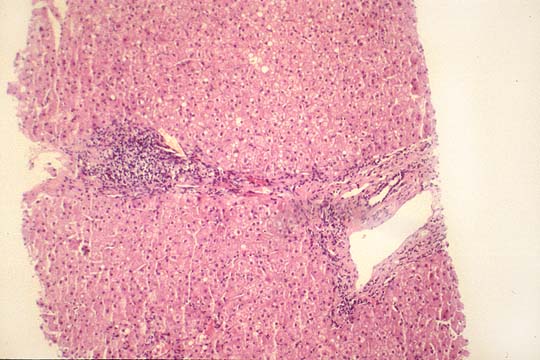

Fig. 121 - Fibrosis

portal-portal.

Viral hepatitis C infection induces the general changes of hepatitis, namely, necroinflammation and fibrosis. These two parameters are morphologically estimated according to the scoring system presented in the discussion of viral hepatitis B. (see contents, li-5-3).As in hepatitis B, the damage of hepatocytes is considered to be immunomediated, (Acadia, Intervirology 37(2):126-132,1994), Although direct viral cytopathogenicity is also probable. A few quantitative differences of pathological changes appear to be associated more with hepatitis C:

8--perivenular fibrosis similar to alcohol.(Uchimura, Liver 15(6):300-6, 1995)